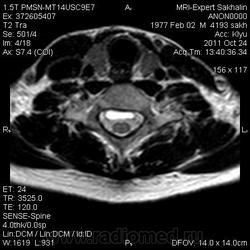

1. Субархноидальная киста

2. Лизированная субдуральная гематома.

3. Менее вероятнее эпиема (но это только при условии соотвествующей клиники...)

Такая огромная гематома на 2 отдела?

Думаю все же №1... № 2 - это запасной вариант. Послушаем, что скажет общественность

Мультилокулярная экстрадуральная менингеальная киста